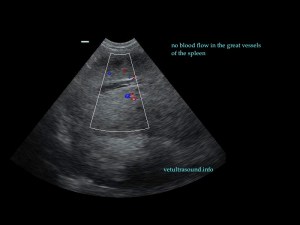

Ευρήματα: Η κεφαλή του σπλήνα βρέθηκε μετατοπισμένη ( στραμένη προς τα οπίσθια άκρα) με υποκαψικές περιοχές υποηχογένειας, χωρίς αιμάτωση (pic 1,2,3). Το τμήμα αυτό του σπλήνα ήταν διογκωμένο σε σχέση με το υπόλοιπο όργανο και το μεσεντέριο λίπος που το περιέβαλε ήταν έντονα υπερηχογενές. Στο συγκεκριμένο σημείο του σπλήνα τα μεγάλα αγγεία δεν είχαν ροή αίματος κατά τον έλεγχο με έγχρωμο Doppler (pic3). Αντίθετα το σώμα και η ουρά του οργάνου είχαν φυσιολογική αιμάτωση και μέγεθος (pic 4,5).

pic1